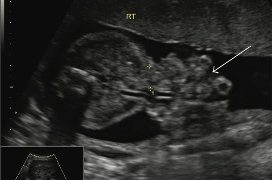

Guida al Counselling di Ottobre 2022: ridotta riserva ovarica e CFA

Cari colleghi, vi presentiamo la guida al counseling di Ottobre relativa alla ridotta riserva ovarica e alla conta dei follicoli antrali!! Potrete scaricarla cliccando sul link. Grazie a Carlotta Zorzi...